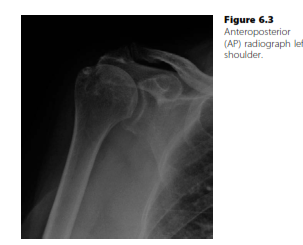

Shoulder and elbow structured oral examination question5 EXAMINER : Good afternoon. Can you tell me the findi…